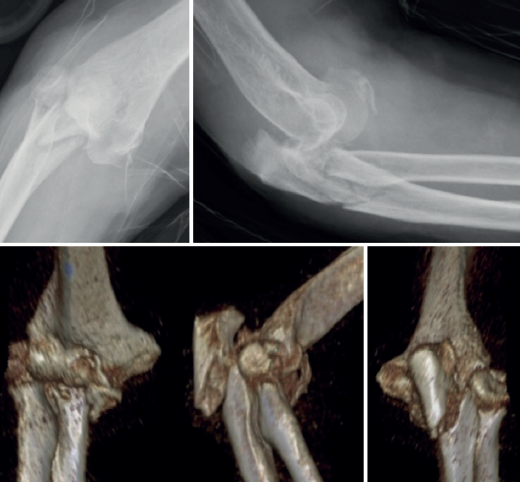

A pesar de que no existe un consenso en relación con la clasificación de las fracturas-luxaciones del codo y ateniéndonos al concepto fractura-luxación transolecraneana, en estas lesiones debe existir una fractura intraarticular del olécranon, con solución de continuidad en la cortical posterior del cúbito, en la que se ve comprometida la estabilidad humerocubital. Si no existe una luxación de la articulación radiocubital proximal, el término adecuado es “fractura-luxación transolecraneana” y, si se asocia una luxación de la articulación radiocubital proximal, “fractura-luxación variante de Monteggia” (Figura 1). Los estudios radiológicos no siempre permiten diferenciar claramente los patrones de fractura por lo que la tomografía axial computarizada (TAC) y especialmente las reconstrucciones tridimensionales son imprescindibles para su diagnóstico.

El desplazamiento del cúbito y del radio con respecto al húmero puede ser anterior o posterior tanto en la fractura-luxación transolecraneana como en la fractura-luxación variante de Monteggia (Figuras 2, 3 y 4). En los adultos, las fracturas-luxaciones transolecraneanas anteriores son menos frecuentes que las posteriores y se diferencian más fácilmente de las fracturas-luxaciones variante de Monteggia de tipo I que las fracturas-luxaciones transolecraneanas posteriores, que frecuentemente se confunden con fracturas-luxaciones variante de Monteggia de tipo II. En ambas lesiones existe una fractura intraarticular del olécranon, pueden asociar una fractura y/o luxación de la cabeza del radio y una fractura de la coronoides y, en las fracturas-luxaciones variante de Monteggia de tipo II, puede asociarse una lesión del ligamento colateral lateral(1,2,13,14,15).